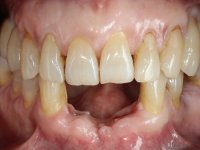

Paciente do sexo feminino com 62 anos, fumadora. 10 Anos atrás tinha sido colocado um implante na zona dos dentes 41 e 42 para reabilitar com uma ponte de dois elementos a falta destes dois dentes. Feito o exame imagiologico foi observada uma perda óssea junto ao implante compatível com uma peri-implantite. A parede óssea vestibular junto ao implante apresentava uma extensa reabsorção, estando a superfície vestibular do implante em contacto com os tecidos moles e numa determinada zona um orifício permitia a visualização do implante através do tecido gengival. Os dentes 42 e 32 apresentavam já alguma mobilidade.